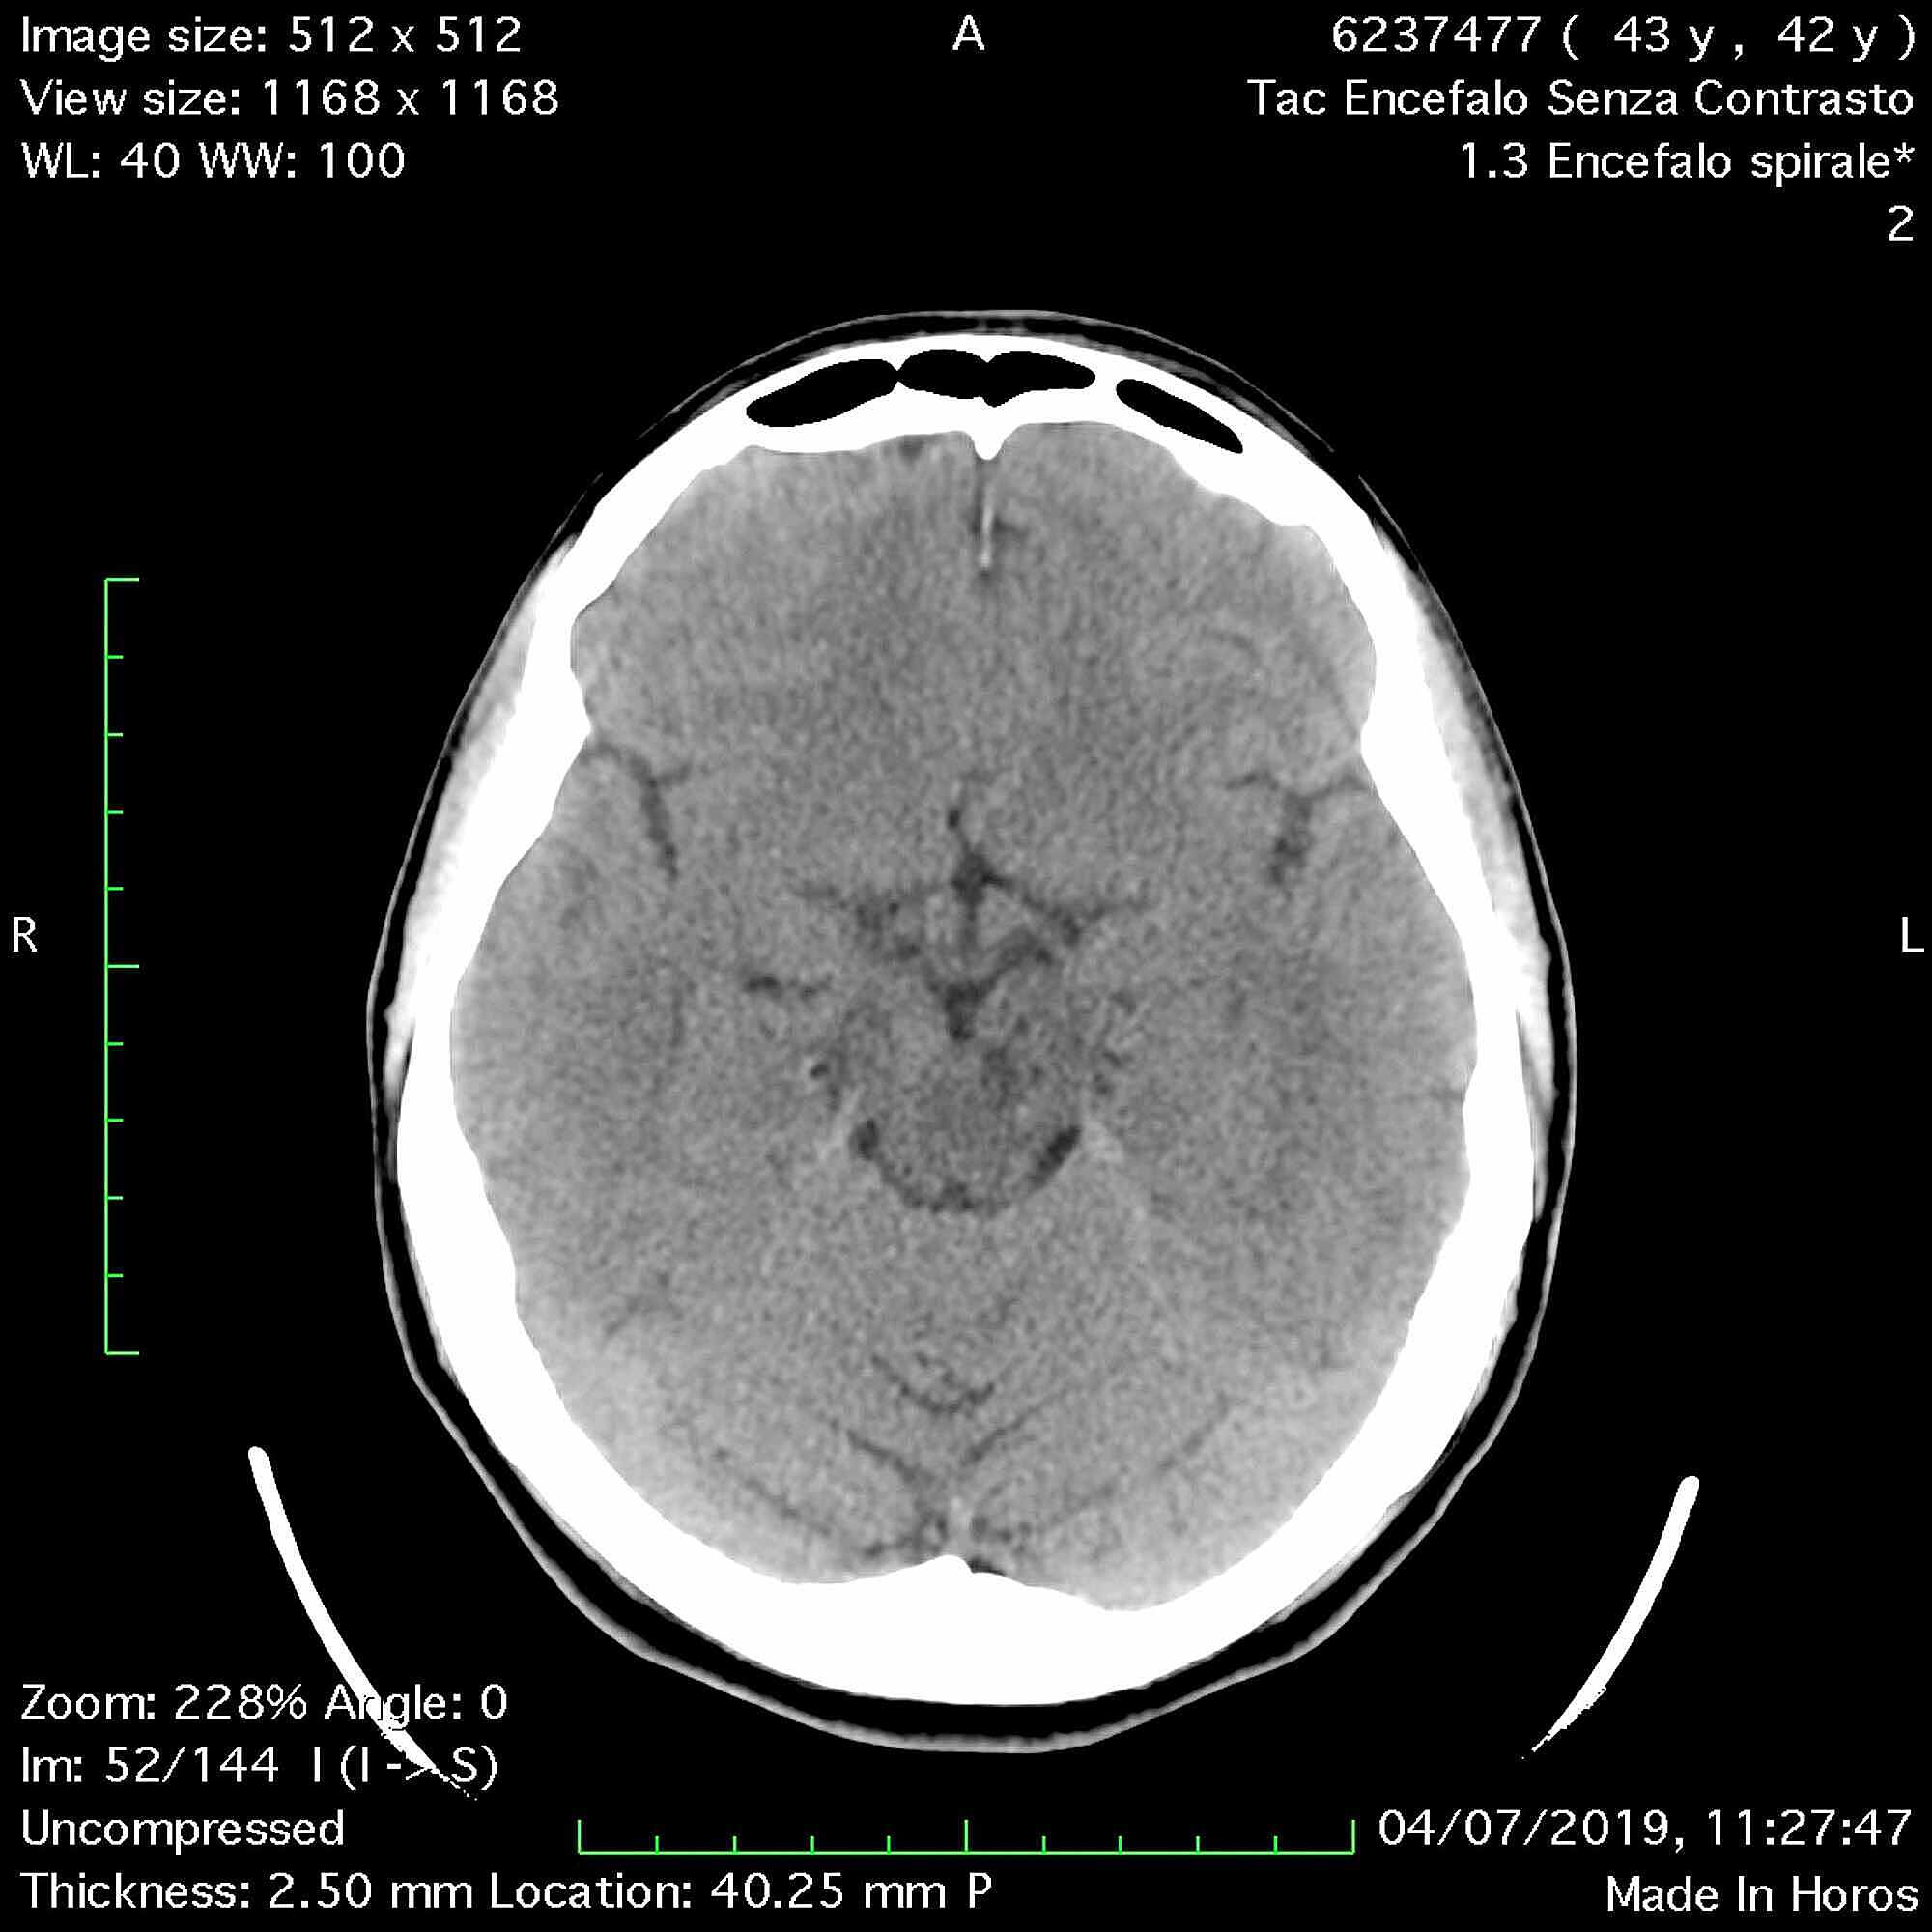

The patient was discharged and she continued the treatment for the scalp lesion and gradually recovered from vertigo. She repeated CT and MRI exams to follow the midbrain lesion up: a CT scan after one month (Figure 5) and a MRI scan after four months (Figure 6). A significant volume reduction of the midbrain lesion was observed.

A recent review discussed the role of mild traumatic brain injury as a cause of VRSs pathological enlargement [5]. Even in our case, we had an enlargement of VRS in the midbrain after a head trauma. The resulting mass effect could explain the neurological symptoms that our patient complained. We can also notice that these findings of enlarged spaces reduce after one month from the trauma: even if this result is in contrast with a previous investigation reported in literature [8] that showed permanent PVSs dilations after mild traumatic brain injuries, maybe it can be explained by the concomitant bleeding as an additional cause of enlargement.